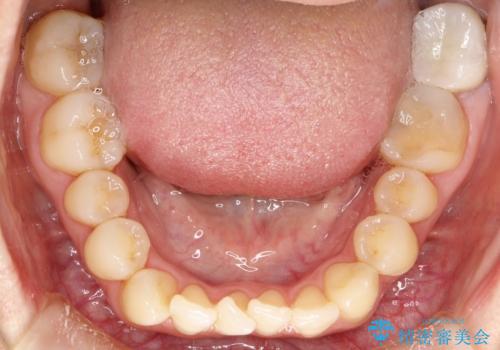

上顎の前歯が前方に傾斜して、下顎の前歯と接触していない状態でした。

上顎の前から4番目の歯を両側抜歯して前歯を後方に移動させる計画としました。